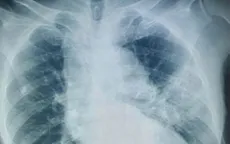

VTV.vn - Một bệnh nhân 80 tuổi suy hô hấp, sốt kéo dài, không đáp ứng kháng sinh, được xác định viêm phổi do Candida albicans, cảnh báo nguy cơ bỏ sót nhiễm nấm xâm lấn.